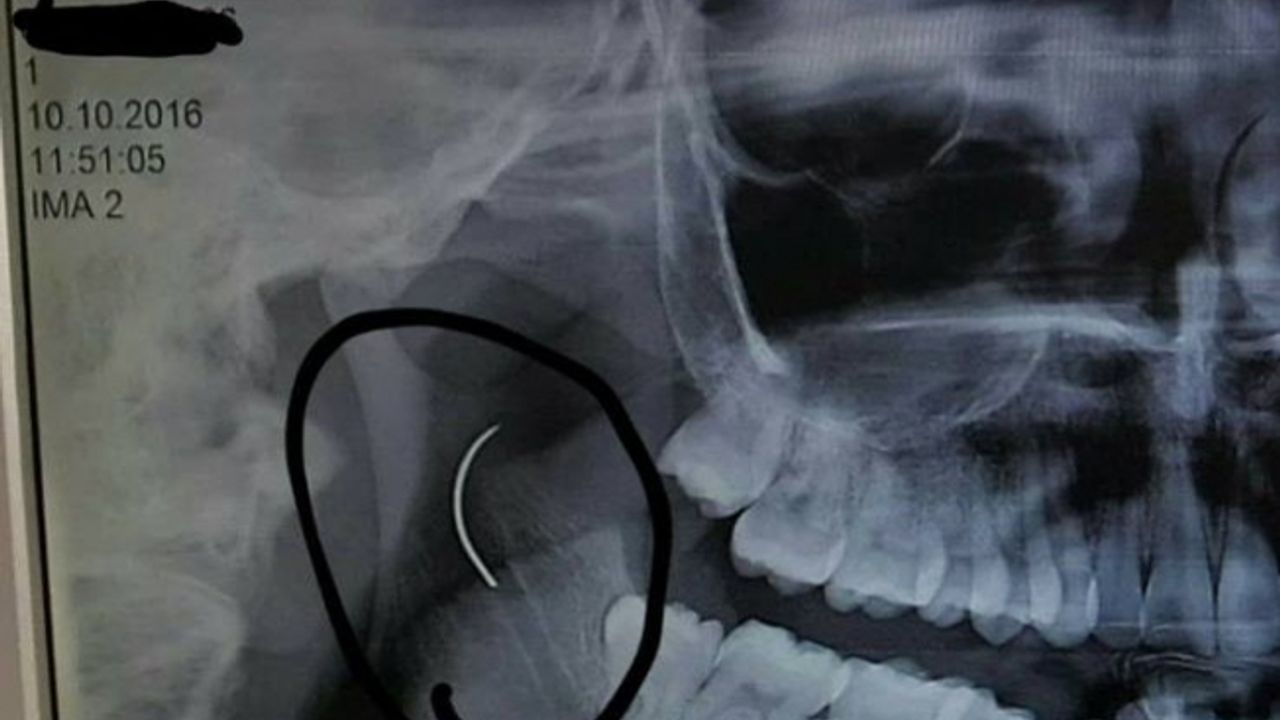

Boğazındaki iğneyle geçen 18 yılını anlatan Meltem Cansız, "3 yaşında geçirdiğim bademcik ameliyatında iğne boğazımda unutulmuş. Daha sonra iğneden dolayı 11 yıl sonra 14 yaşındayken kulak rahatsızlığım ortaya çıktı. Kafamın sağ tarafı ağrımaya başladı. Doktora gittik, hiçbir şey olmadığını söylediler. Sonrasında beni MR çekilmek üzere Akhisar’a yönlendirdi. Gecenin bir vakti MR’a girdim. Ancak bir türlü çekemediler. Benim üzerimde toka vs. metal bir şey olduğunu söylediler baktılar ancak bir şey yoktu. Üç yada dört defa MR’a girdim. Ancak bir türlü çekemediler. Sonra doktorumuz röntgene yönlendirdi. Röntgen görüntüsünde ameliyattan kalma bir çengelli iğnenin boğazımda olduğu görüldü. Bunun için beni Ege Üniversitesi’ne sevk ettiler. Burada doktorlar bu ameliyatı yapabileceklerini ancak riskinin çok olduğunu söylediler. Biz yine de kabul ettik. 1,5 saatlik operasyon geçirdim ancak iğneyi bulmadıklarını söylediler. 2 sene kadar araştırma yaptık. Birçok hastaneyle görüştük. Ancak ayağımda bir rahatsızlık meydana geldi. Ayağım için Ege Üniversitesi’ne gittik. Tekrardan beni ameliyat eden doktorumla görüştüm. ’Seni ben ameliyat ettim, tekrardan buna kalkışamam’ dedi. MR’a da giremezsin dediler. ’Sen bununla yaşamayı öğren’ en azından bunun için çabalama alınmaması daha iyi dediler. Ben daha genç bir kızım sonuçla bu iğneyle ömür boyu yaşayamazdım. Yaşanan bu olumsuzların ardından araştırmalarımız neticesinde en son İzmir’de özel bir hastaneye gittik. Oradaki doktorum Çağlar Çallı bey bana umut verdi. ’Bu iğneyi alacağız’ dedi. İnancımı kaybetmedim, sonucun ne olacağını bilmeden girdim ben o ameliyata. Ölüm, felç olma riskim çok fazlaydı. ’Yaşayamayabilirsin’ dediler, biz bile bile lades dedik. Sonucu da güzel oldu" dedi.

Baba Ahmet Cansız ise kızını 1999 yılında 3 yaşındayken bademcik sorunu nedeniyle Soma Devlet Hastanesi’ne götürdüğünü belirterek, "Bademcikleri nedeniyle çok sık hasta oluyordu. O günkü SSK’da doktorumuz ameliyat olması gerektiğini söyledi. Neticede ameliyat olduk. Ameliyat sonrasında aradan geçen süreçte kızım 17 yaşında geldiğinde yüzünde, sağ tarafında bir ağrının olduğunu, başının, kulağının ağrıdığını söyleyince kulak burun boğaz doktoruna gittik. İlaçlar verdi geçmedi, sonra bir daha gittik. Eklem arası bir iltihap olabilir diyerek MR istedi. Akhisar ilçesine MR çekilmeye gittik. Fakat bir türlü çekemediler. Daha sonra bir film çekildi ve iğne ortaya çıktı" diye konuştu.

Ege Üniversitesi’ne gittiklerini belirten baba Cansız, iğnenin şah damarına çok yakın olduğunun söylendiğini belirterek şunları söyledi: "Doktorlar çok tehlikeli bir ameliyat olacağını yanlış ya da en ufak bir hatada kızımızın bir tarafının felç kalabileceğini veya hayatını kaybedebileceğini söylediler. Biz bu riski göze alarak ameliyata müsaade ettik. Fakat iğneyi görüldüğü yerde bulamadıklarını söyleyerek alamadılar. Sonra İzmir Çiğli’de özel bir hastanede denedik. Kendisine binlerce kez teşekkür. Allah razı olsun. Çocuğumun boğazındaki iğneyi aldı. Dünyalar bizim oldu."